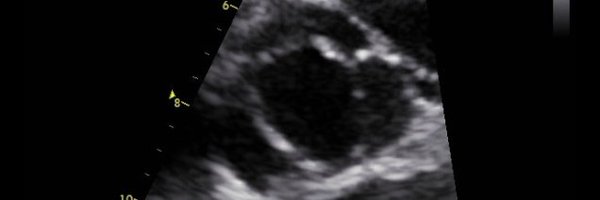

🧐Eje corto GV VÁLVULA Aórtica bicuspide fusionada D-I